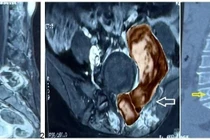

Tại Bệnh viện Nhi đồng 2, bệnh nhi được chỉ định siêu âm, CT-Scan và xét nghiệm máu. Kết quả cho thấy, bé mắc u tế bào mầm sau phúc mạc và được nhập khoa Ung bướu – Huyết học để theo dõi, điều trị.

Do cấu trúc mạch máu vùng bụng phức tạp, hình ảnh CT-Scan cho thấy khối u đã che khuất tĩnh mạch chủ dưới – tĩnh mạch lớn nhất của ổ bụng cùng cuống mạch máu thận. Ê-kíp phẫu thuật phải tiến hành bóc tách cẩn thận để bảo tồn các mạch máu quan trọng, tránh gây tổn thương trong quá trình mổ.

Sau 5 giờ phẫu thuật, các bác sĩ đã bóc tách thành công khối u nặng 1,3 kg. Sau mổ, bệnh nhi hồi phục tốt và tiếp tục được hóa trị theo phác đồ điều trị.